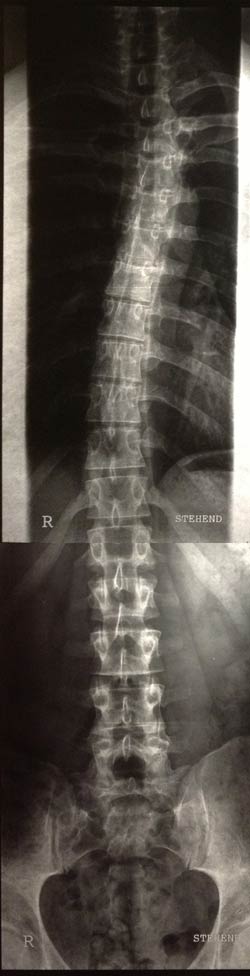

So, hier sind sie:

Was sagt ihr dazu? Welche Therapie ist zu empfehlen. Schroth zahlt die Kasse hier nicht. Irgendwelche Gedanken?

Die Skoliose ist ja hauptsächlich im Bereich der BWS, wie man erkennen kann.

- Dateianhänge

-

- BWS

- Foto-4.jpg (28.35 KiB) 14515 mal betrachtet

- LWS

- Foto-3.jpg (28.45 KiB) 14515 mal betrachtet

Kyphose (seitliche Aufnahme) müsste im grünen Bereich liegen

Skoliose, so ganz grob ca. um die 16 Grad.

LWS sieht doch ordentlich aus. Guter Abstand in den Bandscheibenfächern L 3,4,5

aber wenn dort eine Bandscheibe defekt sein soll, dann frage ich mich welche.

Weiter oben vermutlich bei L1, L2.

Aber das Becken steht irgendwie krumm da oder sieht das nur so aus, weil man

nicht alles sehen kann.

ich finde die Kyphose schon relativ deutlich im BWS-Bereich, die skoliotische Abweichung ebenfalls. Eventuell macht die Kombination von beidem die von Dir beschriebene Problematik. Aber das lässt sich via Internet nicht definitiv sagen. Dazu müsste man zum einen Dich "live" vor sich stehen haben und zum anderen die Bilder auf Folie in Originalgröße. An diesen kann man auch den Winkel ausmessen. Ausdrucke eignen sich zur Befundung nicht.

Es fällt eine Steilstellung der HWS, eine leichte Hyperkyphose und eine leichte Skoliose auf und mit Schroth könntest Du wahrscheinlich ganz gute Ergebnisse erzielen.